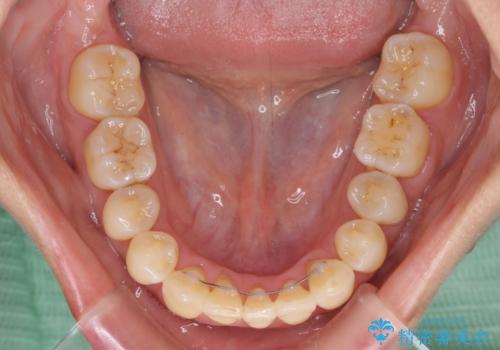

通常であれば、上下顎左右小臼歯各1歯の合計4本を抜歯しますが、歯肉退縮の著しい下顎前歯を抜歯して欲しいという患者様の強い希望により、上顎のみ左右小臼歯2歯を、下顎は前歯を1歯を抜歯することとしました。

抜歯する歯を変更したため奥歯の咬合はアンバランスとなりましたが、前歯は綺麗に整い、歯肉退縮も回避できました。